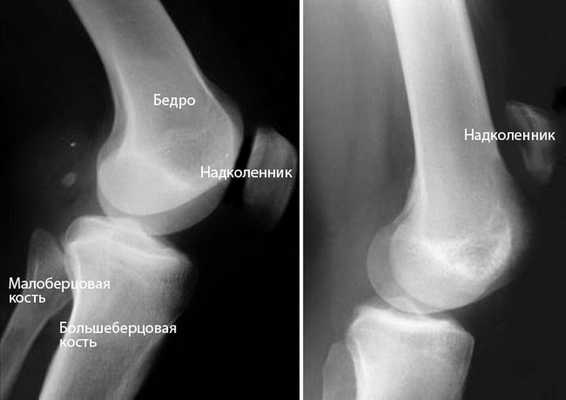

Диагноз выставляется на основании анамнеза, характерных клинических проявлений и данных дополнительных исследований. Инструментальные и лабораторные методики в большинстве случаев малоинформативны, назначаются для дифференциальной диагностики, исключения осложнений, выявления вторичных, длительно текущих или оссифицирующих тендинитов. Программа обследования может включать следующие процедуры:

- Рентгенография коленного сустава. Обычно без изменений, иногда на снимках заметно незначительное утолщение мягких тканей. При оссификации в ткани сухожилия обнаруживаются очаги обызвествления.

Провести физический осмотр коленного сустава сразу после получения травмы удается не всегда, потому что сильно болит собственная связка. Чтобы установить точный диагноз, применяется инструментальный метод - рентген. После разрыва мышцы происходит смещение надколенника, так как он оказывается без поддержки. Но бывает и так, что надколенник у человека находится в смещенной позиции по причине анатомических особенностей опорно-двигательного аппарата.

Чтобы диагностировать травматическое повреждение, делается рентген обеих конечностей. Для получения максимально точной и развернутой информации относительно состояния надколенника и его связок для диагностики разрывов применяются дополнительные инструментальные методы - УЗИ и магнитно-резонансная томография: